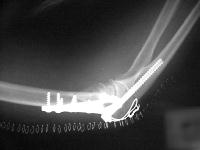

Initial fixation:

Films on arrival, one week after surgery. Neurovascular exam is normal. Early loss of fixation.

The fracture complex was assessed as the following, with central comminution - Posterior view:

The lateral epicondyle was found to have additional coronal comminution - Lateral view:

The medial column had a narrow proximal cortical strut remaining - medial view: